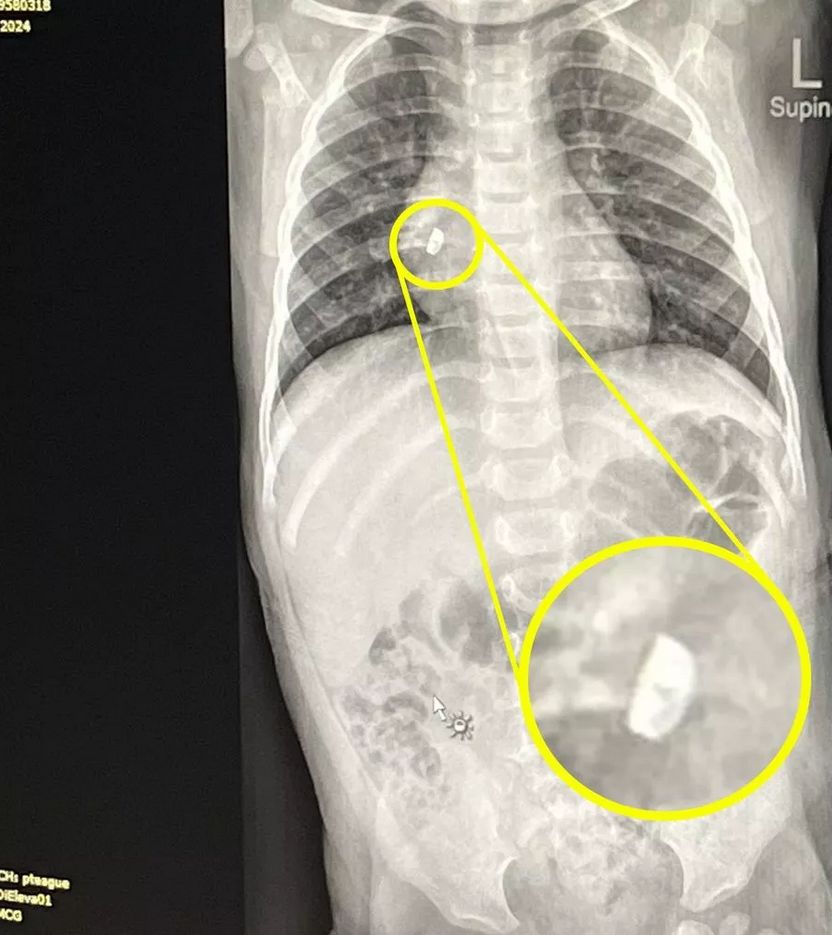

Kolejna wizyta u lekarza i zalecone prześwietlenie odsłoniły szokującą prawdę: w płucu Raelyn tkwił niewielki metalowy przedmiot. To była część kolczyka.

- Na myśl o tym, że ewentualne zapalenie płuc czy komplikacje mogłyby zagrozić jej życiu, serce mi stawało – przyznaje mama. Kolejne badania potwierdziły, że kolczyk tkwił głęboko w prawym płucu. Konieczna była operacja.

Lekarze użyli specjalnego magnesu, aby wydobyć metalowy fragment. Operacja zakończyła się sukcesem, a Raelyn spędziła noc w szpitalu na obserwacji. Następnego dnia szczęśliwi rodzice zabrali ją do domu.